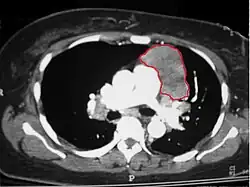

When a thymoma is suspected, a CT/CAT scan is generally performed to estimate the size and extent of the tumor, and the lesion is sampled with a CT-guided needle biopsy. Increased vascular enhancement on CT scans can be indicative of malignancy, as can be pleural deposits.[2] Limited biopsies are associated with a very small risk of pneumomediastinum or mediastinitis and an even-lower risk of damaging the heart or large blood vessels. Sometimes thymoma metastasize for instance to the abdomen.[6]